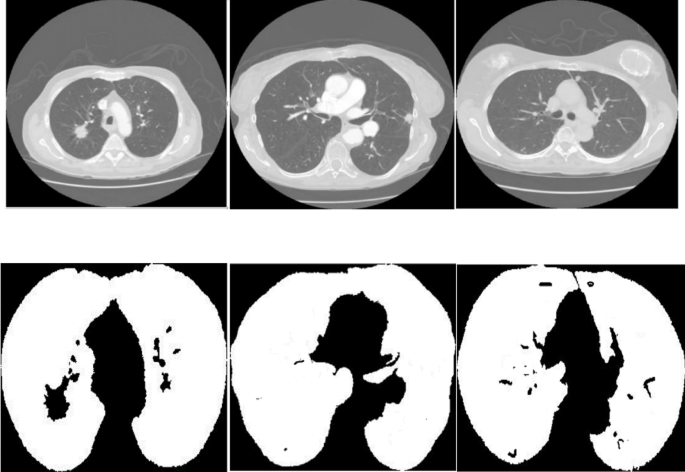

The discriminator in the 3D reconstruction stage is designed to evaluate the realism of volumetric images generated by the GAN-based architecture. It receives as input the reconstructed 3D lung tumor volumes produced by the generator. The discriminator compares these generated volumes with the corresponding real, annotated 3D ground-truth data to evaluate the structural authenticity. To evaluate these 3D volumes, the discriminator employs 3D dilated convolutional layers. This structure enables it to analyze spatial dependencies in all three dimensions and detect inconsistencies in the generated structures. The output is a scalar prediction score that reflects the anatomical plausibility of the reconstructed volume. During training, EMD is employed as a global evaluation criterion, quantifying the distributional shift between real and synthetic 3D data across spatial regions. In contrast to earlier stages, where the discriminator evaluates 2D binary masks or region proposals, it operates on entire 3D reconstructions here. The discriminator acts not only as a classifier but also as a spatial coherence assessor, ensuring the generated volumes exhibit consistent shape, texture, and continuity over slices. This feedback loop encourages the generator to refine outputs that are both anatomically consistent and visually coherent in the volumetric space.

Algorithm 2 shows the training procedure for the proposed TLSTM-based 3D tumor reconstruction model. The process begins with a training dataset composed of sequences of 2D tumor-detected slices, each annotated with a corresponding 3D ground-truth volume. Each slice from the input sequence is processed by a pre-trained EfficientNet encoder. This step extracts important high-level features from each image. A spatial attention mechanism is then applied to enhance the focus on anatomically relevant regions such as tumor boundaries. These focused features are sent to a TLSTM module. This module updates its hidden and cell states at each step to preserve temporal consistency across the slices.

The hidden state sequence contains both spatial and temporal information. This sequence is passed to a generator network that reconstructs the full 3D tumor volume. The training loss comprises two components: the mean absolute error (MAE) between the predicted and actual volumes and an adversarial loss. The adversarial loss is scaled using a hyperparameter. Gradients are backpropagated to update the parameters of the generator and the TLSTM units. This process gradually improves the quality of 3D reconstructions throughout training epochs.

Overall algorithm

Figure 9 provides a comprehensive overview of the 3D reconstruction of lung tumors, outlining the step-by-step process from initial CT image acquisition to the final evaluation of the reconstructed 3D model. The flowchart starts with the input of a series of CT images from a patient, labeled as \(\:\{{I}_{i},\:M\}\), where \(\:M\) is the target 3D image derived from the sequence of \(\:{I}_{i}\) images. This target image is crucial as it serves as the benchmark for assessing the performance of the reconstructed 3D model. The rest of the stages are shown in the following:

-